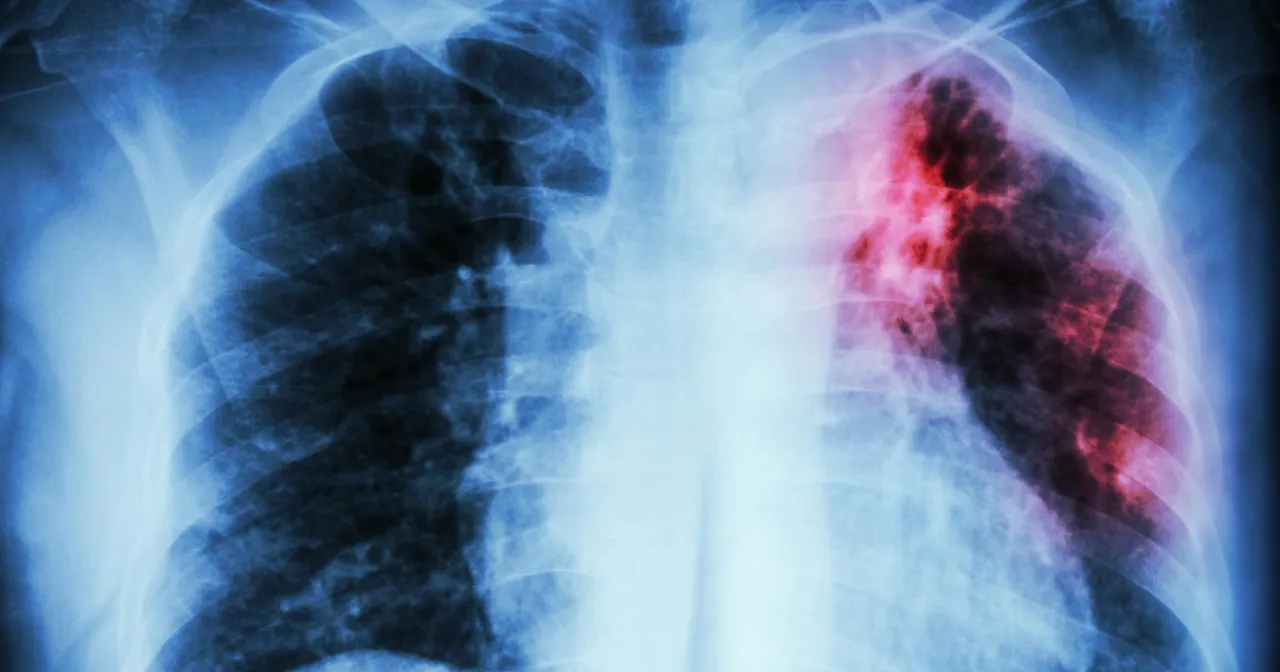

Charakterystyczne objawy gruźlicy płuc

Gruźlica płuc objawy daje przede wszystkim w postaci uporczywego kaszlu. Kaszel początkowo jest suchy, później pojawia się odkrztuszanie śluzowej lub ropnej wydzieliny.

Chorzy mogą odczuwać bóle w klatce piersiowej i duszności. U niektórych pacjentów występuje krwioplucie.